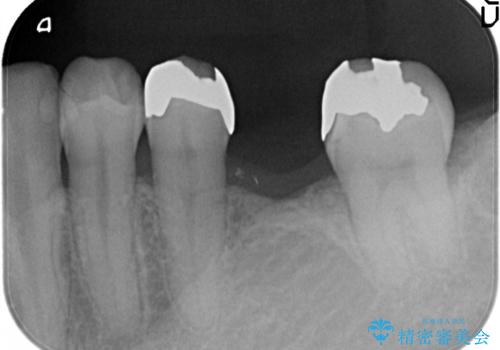

- 奥歯の補綴治療を主訴に来院されました。

今回はブリッジでの補綴を希望されたため、オールセラミッククラウンにより治療を行っております。

今回は両隣在歯に修復治療が行われており、外科治療を伴わないブリッジにて修復を希望され治療を行っております。